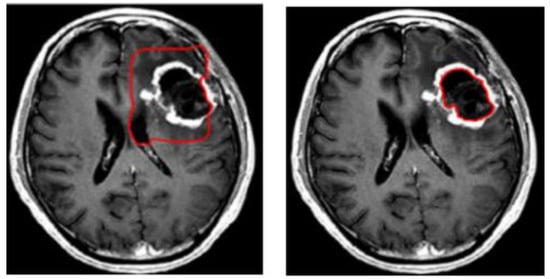

3.3. Level Set Segmentation

| 1: Insert initial contour points using two-step DA clustering output (ROI indexes). 2: Construct a signed distance function. 3: Calculate feature image using Gaussian filter and gradient. 4: Obtain the curve’s narrow band. 5: Obtain curvature and use gradient descent to minimize energy. 6: Evolve the curve. 7: Repeat step number two and stop after obtaining the segmented region. |